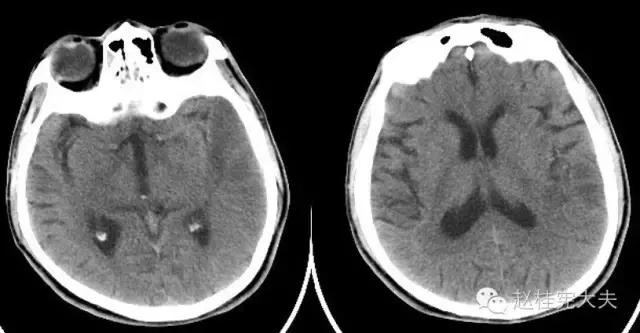

入院前1天的头颅CT:

定位诊断:混合性失语,定位于左侧大脑半球语言中枢(运动和感觉),右侧中枢性面舌瘫,定位于左侧面神经核团以上,右侧上下肢肌力下降,病理征阳性,定位于左侧锥体束。感觉、视野查体无法配合,暂无相应定位考虑。综合考虑,定位于左侧大脑中动脉分布范围。头颅CT:左侧颞叶片状低密度影,左侧大脑中动脉下干支配区,支持临床定位。

定性诊断:结合57岁,男性,急性病程,逐渐加重,进展性右侧肢体无力、混合性失语。头颅CT:左侧颞叶片状低密度影。脑梗死为首先考虑,左侧大脑中动脉支配区,大动脉粥样硬化型。尽管患者本人无高血压、糖尿病等危险因素,但患者母亲有中风、糖尿病史,存在家族中风危险因素,故待完善血生化及血管等卒中危险因素筛查。入院后继续急诊抗血小板、降脂稳定斑块及脑保护治疗。